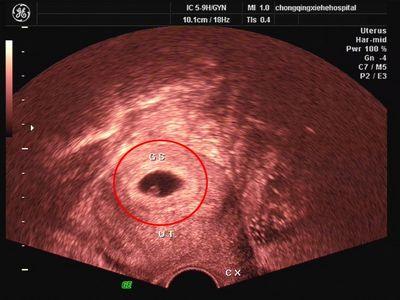

阴超,又称腔内B超,是将B超探头放入阴道或者直肠进行超声诊断的方法,特别适合于观察小骨盆内的盆腔脏器,图像更加清晰逼真、显示率高,结果更准确,减轻憋尿痛苦,为孕妈妈节省时间。

(阴道B超)

在孕早期的时候,如果通过B超不能看到的情况,都可以借助阴道超声检查,检查时,医生会在探头上套层薄膜(一般使用避孕套)做保护用,然后将探头轻轻插入阴道进行检查,进入大约4-5厘米,并不会增加流产的风险,一般也不会有太大的疼痛感,最多就是会有些不适,一般都是可以忍受的,建议大家在做阴超的时候放轻松,不要给自己太大压力。